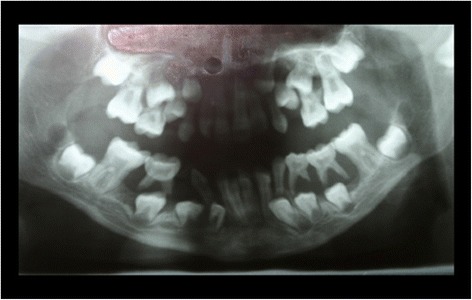

The intraoral examination at the Department of Periodontics, University of Duesseldorf revealed erythematous and hyperplastic gingiva in the upper and lower jaw and Class 3 mobility of all of the deciduous teeth [13]. The panoramic radiograph showed severe generalized alveolar bone loss (Figure 1). The histological assessment of a gingival biopsy was taken buccaly from the second milk molar in the right lower jaw and showed a reactive squamous epithelial hyperplasia with localized fibrin precipitation and massive ulcerations. As the patient did not present for the follow-up appointments, no periodontal therapy was rendered at the time.

Figure 1.

Panoramic radiograph at the age of 9 years: exhibiting signs of untreated periodontal disease.